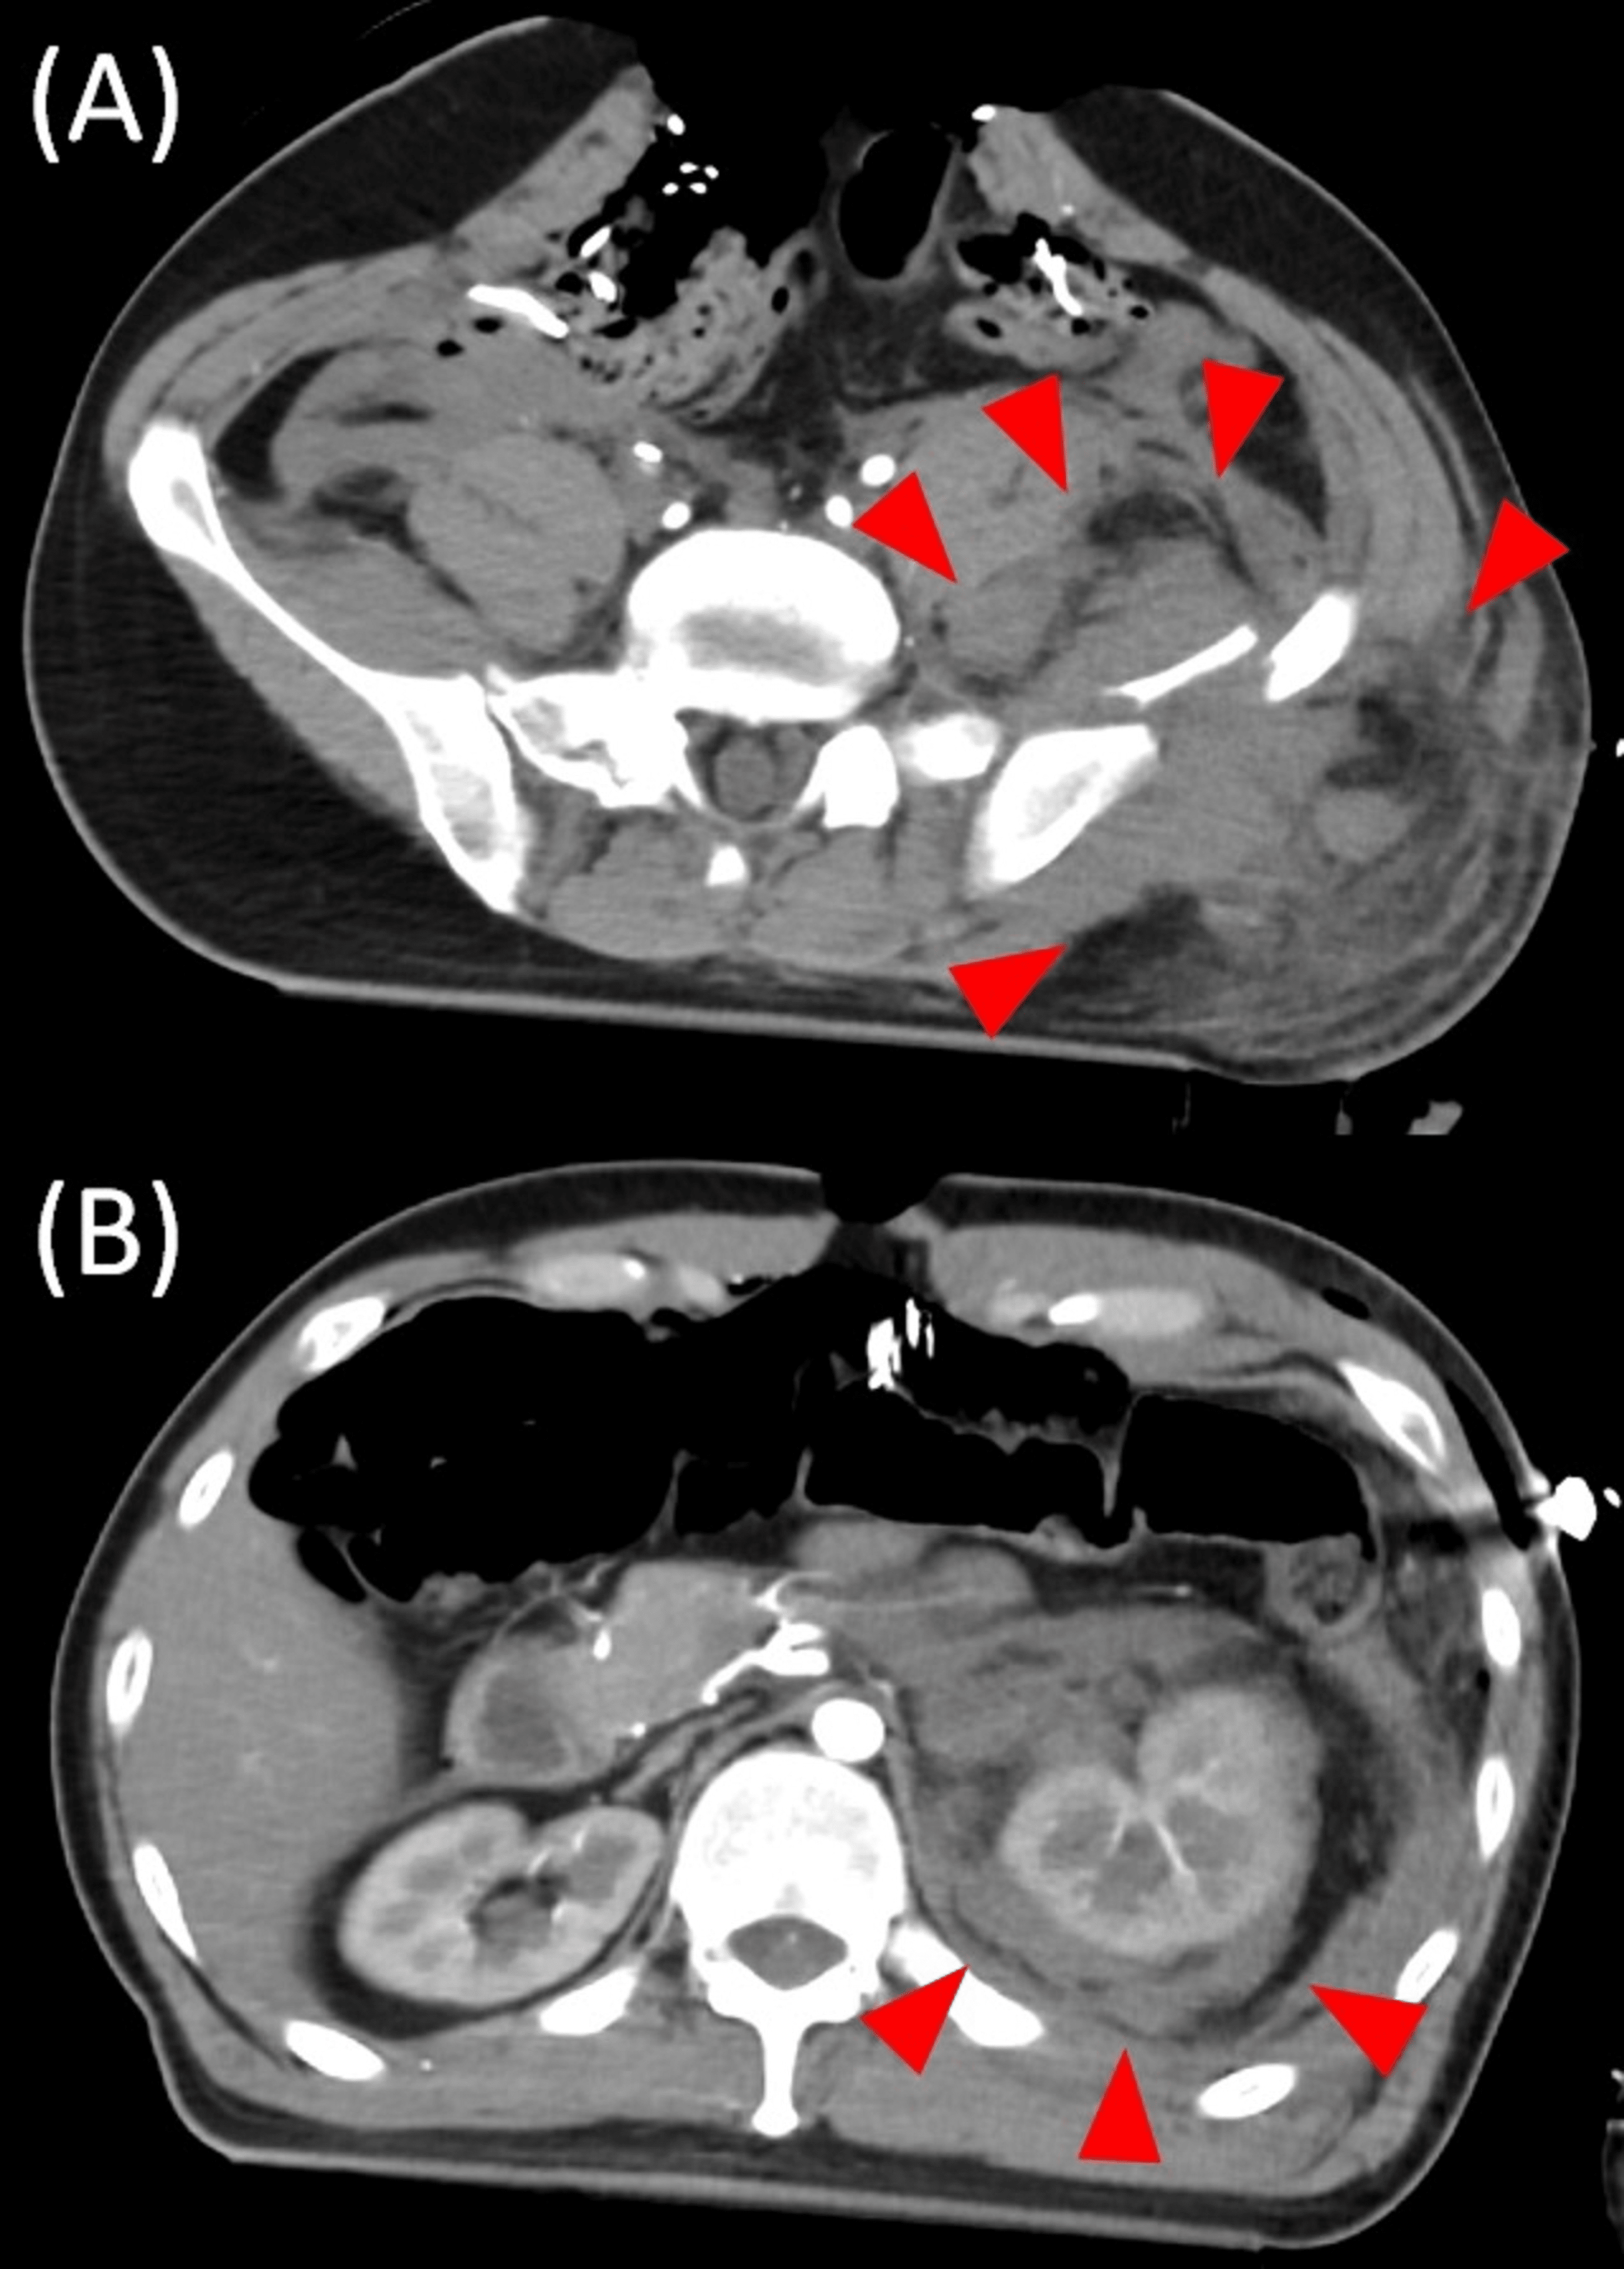

From www.semanticscholar.org

Figure 2 from A case of spontaneous urinary bladder rupture secondary Can A Bladder Rupture From Urinary Retention Urinary retention is when your bladder doesn’t empty completely or at all. Spontaneous rupture of the urinary bladder (srub) is extremely rare and might be misdiagnosed, leading to a high mortality rate. To perform a systematic review of all cases of spontaneous rupture of the urinary bladder (srub) and to describe the demographic data, associated comorbidities,. Untreated urinary retention can. Can A Bladder Rupture From Urinary Retention.